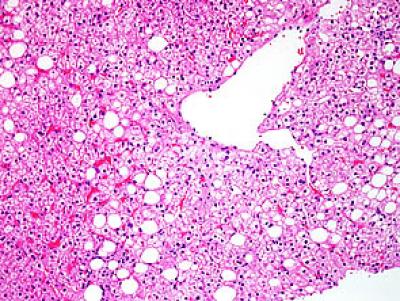

NALFD is the most common liver disease in the United States, affecting up to one third of American adults. It's characterized by abnormal fat accumulation in the liver. The specific cause or causes is not known, though obesity and diabetes are risk factors. Most patients with NAFLD have few or no symptoms, but in its most progressive form, known as nonalcoholic steatohepatitis or NASH, there is a significantly heightened risk of cirrhosis, liver cancer and liver-related death.

The current paper is based on analyses of 600 liver biopsies of patient's with NAFLD by a national panel of pathologists who had no identifying clinical information about the samples. The study excluded anyone who averaged more than two alcoholic drinks per day or who reported consuming five or more drinks in a day (binge-drinking) at least once a month. All of the patients were at least 21 years of age.